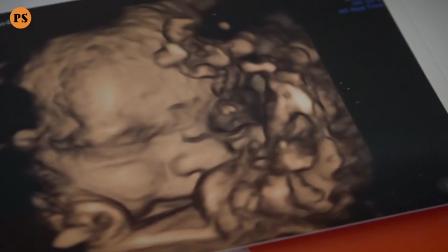

Séta az erdőben

Category: pets & animals